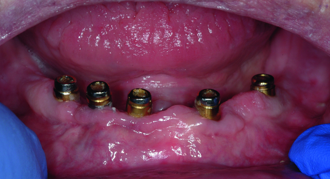

Treatment options for the edentulous arch

Historically, when a patient’s dental condition reached a state of total tooth loss, treatment was limited to a complete denture with no hope of ...

News Mon. 13. October 2014

Contribution of CAD/CAM technology to implant-supported screw-retained restorations

In dental implantology, the optimal and truly passive fit of the framework is essential for the long-term success of a restoration owing to the physiology ...